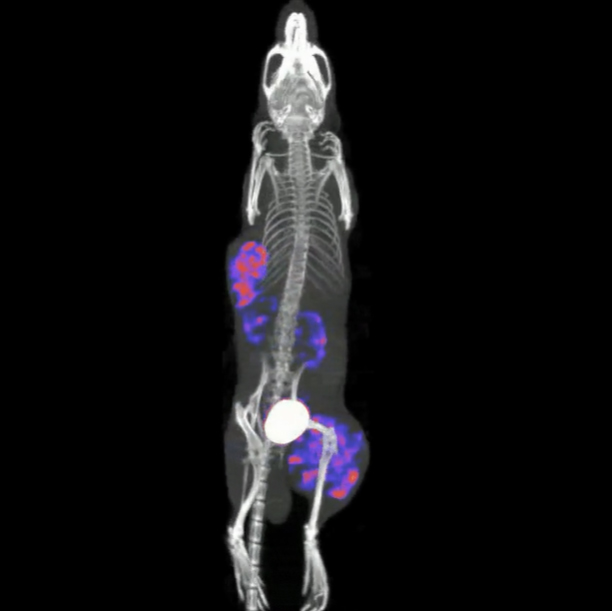

小鼠的高分辨率骨骼成像技术

超高分辨率多针孔准直器能够清晰地展示出小鼠骨骼的精细细节:单个椎骨和肋骨;前臂的桡骨和尺骨。

〉动物:20克小鼠

〉放射性示踪剂:37 MBq(1 mCi)99mTc - MDP

〉准直器:用于全身小鼠成像的超高清多针孔成像系统

〉采集:螺旋SPECT